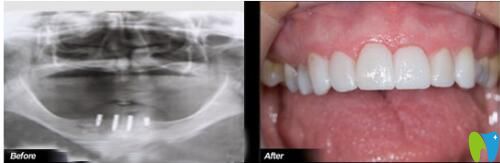

68歲叔叔在歡樂仁愛口腔做完種植牙前后對比照